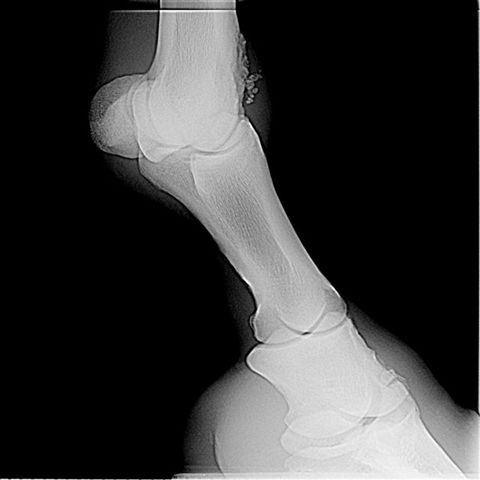

LF lat

The horse has remarkable bone fragments in the coffin, pastern, and fetlock joints. All appear to be osteochonDrOsis type fragments. While no one can predict the future the severity of the lesions suggest a high likely hood of developing osteoarthritis in these joints. Surgery to remove the fragments will improve the prognosis but the multijoint nature and severity of the lesions still would have a guarded prognosis in my judgement.